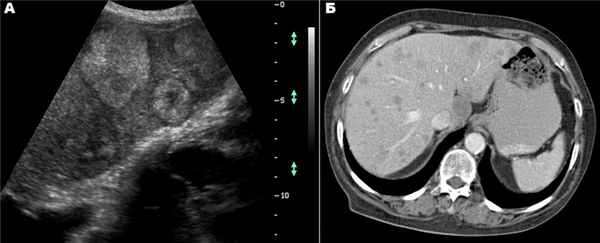

Эти признаки надежны только в случаях отсутствия хронических или острых диффузных заболеваний печени, которые сами по себе могут вызывать изменения вышеприведенных тестов. Существенную помощь оказывает использование УЗИ и КТ (или ЯМР) с болюсным контрастированием, обладающие высокой разрешающей способностью.

Большинство кист небольшие (диаметром 1-5 см), чаще встречаются у женщин. Значительная часть их имеет бессимптомное течение. У ряда больных отмечаются боли в правом подреберье, у одних — постоянные, у других — периодические. Существенную помощь оказывает использование УЗИ и КТ (или ЯМР), обладающие высокой разрешающей способностью. Необходимо учитывать возможность поликистоза печени.

Важную информацию дают инструментальные исследования. Радионуклидная сцинтиграфия печени выполняется, как обычно, при подозрении на объемный процесс в печени в двух проекциях. Благодаря этому методу, как правило, можно обнаружить опухоль диаметром 4-5 см. При гемангиомах диаметром 4-5 см и более опухоль выявляется у 70-80% обследованных. УЗИ при наличии гемангиомы позволяет выявить гиперэхогенное, хорошо очерченное образование. Подобную же информацию представляет ЯМР. Нередко, особенно в менее массивной левой доле, отчетливо видна сосудистая ножка. Гемангиомы диаметром 3-5 см и более выявляются при УЗИ у 70-80% обследованных. Иногда отмечаются в гемангиомах участки обызвествления.

КТ позволяет получить данные, близкие к результатам УЗИ, хотя нередко приносит и существенную дополнительную диагностическую информацию. Эта дополнительная информация в первую очередь касается состояния окружающих ткаей и органов. Целиакография при распознавании гемангиом позволяет получить наиболее точные данные. Обычно хорошо видны гиперваскуляризованные участки с четкими границами, позволяющие обнаружить гемангиому диаметром 2-3 см и более у 80-85% обследованных.